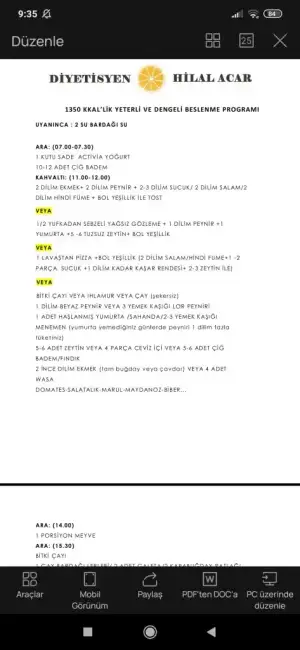

Değerlerim böyle.

Anlayan var mı?

İlaç içmeme multivitamin vs takviyeye gerek var mı sizce?

Hamilelerde bu değerler kaç olmalı.